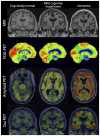

Figures